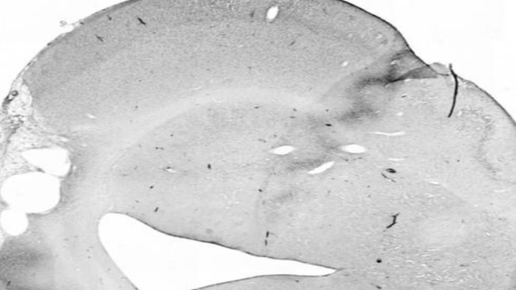

Введение моноклональных антител через нос с помощью капель настолько же эффективно, как и их введение при инъекции в спинномозговой канал у крыс. Концентрация и распределение антител в мозге оказались сопоставимы. Как сообщается в журнале Proceedings of the National Academy of Sciences, такой способ доставки лекарства в центральную нервную систему не повлиял на эффективность антител при восстановлении ткани мозга после инсульта у крыс. С помощью антител врачи и ученые стараются лечить пациентов с нейродегенеративными заболеваниями — например, болезнями Альцгеймера или Паркинсона...